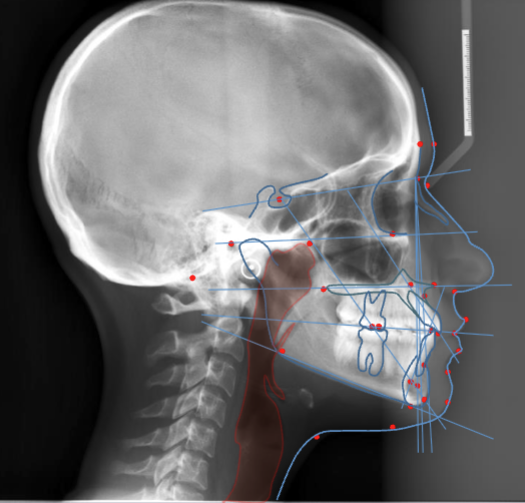

lateral ceph is used to assess what

nasopharyngeal soft tissues + paranasal sinuses